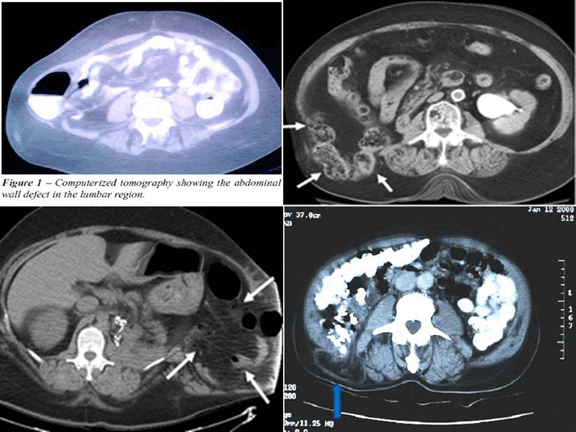

Four patients, three male and one female, with age ranging from 30–50 years (mean age 40 years), presented with a gradually enlarging swelling in the loin. (Figure 1) Three had swelling on the right side and one on the left side. The swelling enlarged in size on coughing and straining and was reduced in supine position. Dragging pain was present in all cases at the site of the swelling. Two patients had multiple small ulceration over the swelling at the time of presentation. There were no associated co-morbid conditions in any patient. (Table 1) There was no notable etiology like trauma or surgery in any patient. On examination impulse on cough was positive with incomplete reducibility in all patients. Mild tenderness was present in the abdomen. Auscultation revealed bowel sounds over the swelling. Ultrasound and CT scan revealed hernia in right lumbar region containing small bowel. (Figure 2)

Figure 2: Computed tomography scan showing lumbar hernia with bowel as contents of hernia in all four patients.